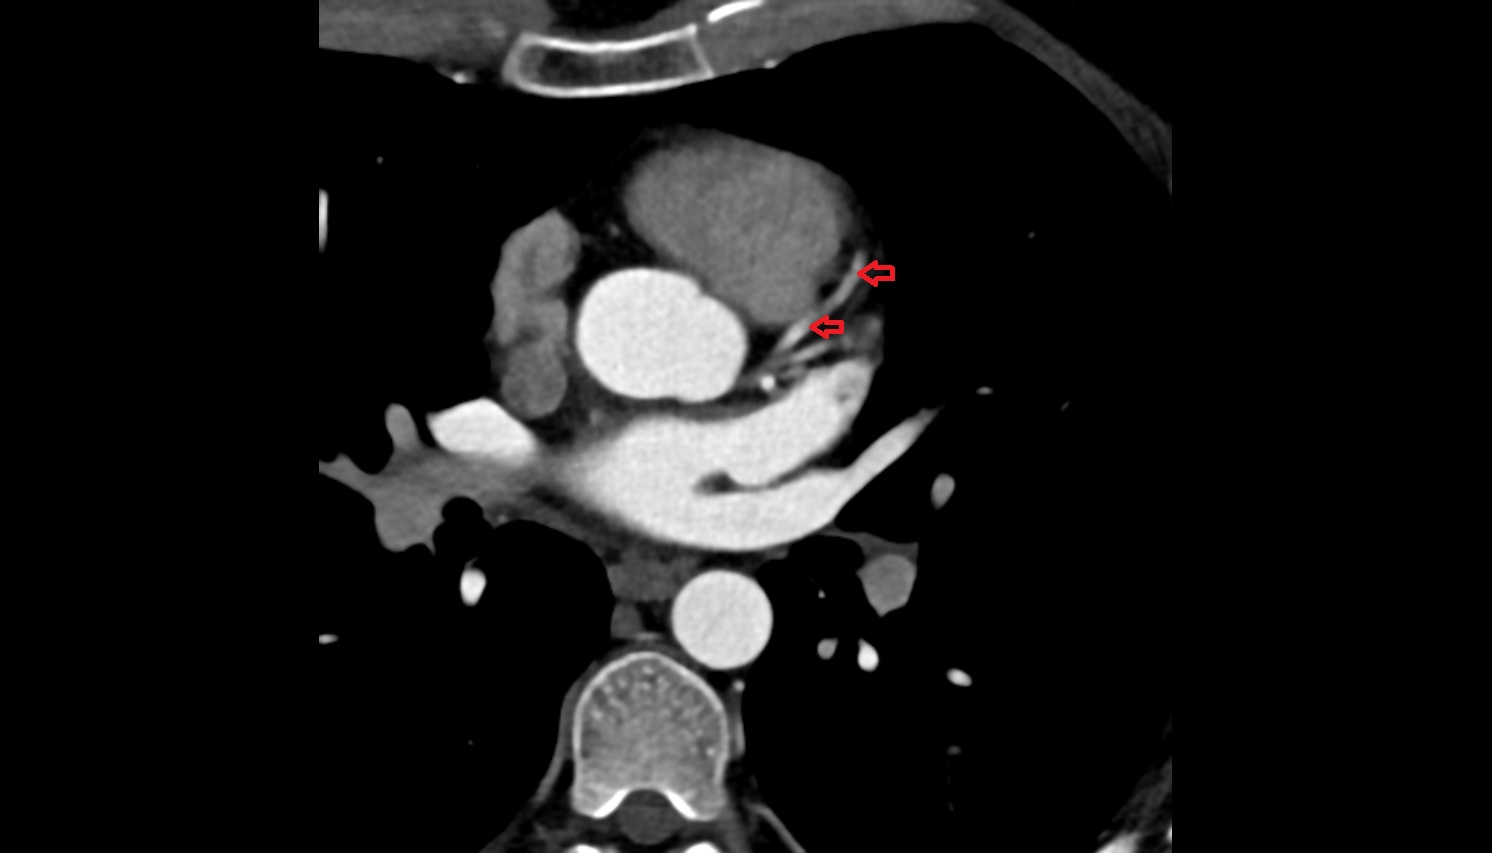

- Left anterior descending artery (LAD)

- Circumflex artery (LCx)

- Left main coronary artery (LMCA)

- Right coronary artery (RCA)

- First diagonal branch (D1) of LAD